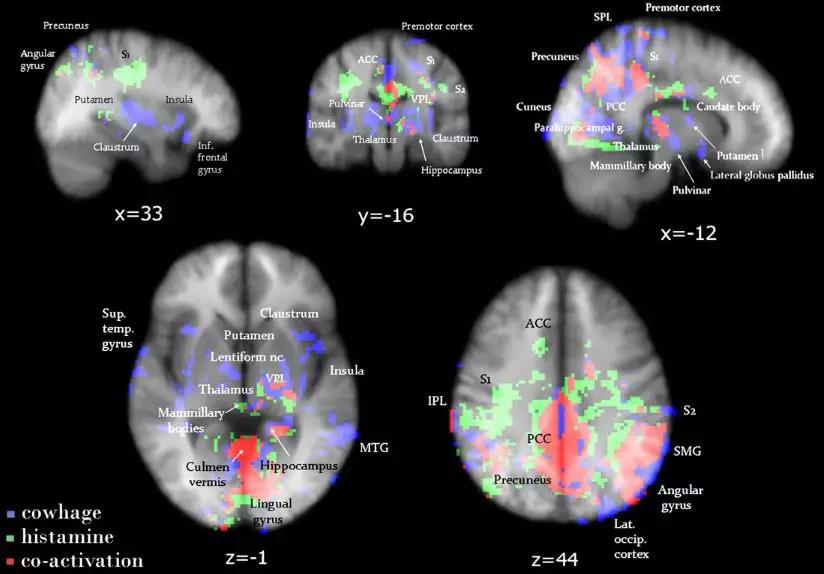

目前尚未有研究能明确指明某个脑区是痒觉感受或是调控的中心。脑影像学研究发现,组胺和黧豆蛋白酶激活的脑区存在差异。这说明不同的致痒刺激激活的脑区也存在着差异。

▲绿色的是组胺激活的脑区,蓝色是黧豆蛋白酶激活激活的脑区,红色是二者共同激活的脑区。